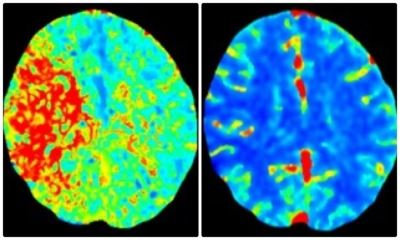

Next up in the fast-moving chain of events was more advanced brain imaging to determine if surgery was required: a CT angiogram and CT perfusion. This color-coded perfusion scan showed the area of Julie’s brain that was inadequately supplied (or perfused) with blood—the red area pictured left. A different but essential view showed that same large area of brain tissue has normal blue color (right). This meant that the red, injured area of her brain could be saved from permanent damage if its blocked blood flow could be emergently restored.